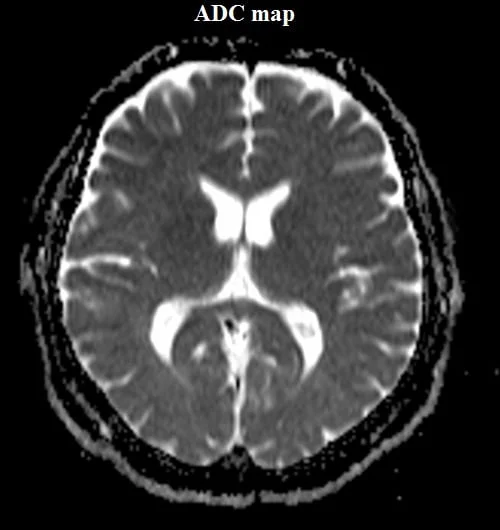

ADC map created from B0, B500, and B1000.

In addition to the diffusion-weighted raw data images, there is another way to present diffusion data known as the apparent diffusion coefficient (ADC) map of water. These maps are calculated from diffusion-weighted images after the acquisition.

MRI image appearance Apparent Diffusion Coefficient (ADC) map

An Apparent Diffusion Coefficient (ADC) map is a specialized image that is crafted by utilizing data from diffusion-weighted magnetic resonance imaging (DW MRI). The ADC value corresponds to the apparent diffusion coefficient of water molecules in a given tissue, showcasing the pace at which these molecules disperse and traverse within the tissue. The movement of water molecules is impacted by factors like cell density, cellular obstacles, and tissue microstructure within biological tissues. This leads to a diversity of ADC values across different tissues and under varying conditions.

- High ADC Value Areas: In regions with high water diffusion, such as fluids or areas with fewer cellular structures, ADC values are high. On the ADC map, these areas typically appear brighter or lighter in color. For example, cerebrospinal fluid-filled spaces in the brain or cystic structures might exhibit high ADC values, appearing bright on the map.

- Low ADC Value Areas: Tissues with restricted water diffusion, often due to increased cellularity or compactness, have low ADC values. On the ADC map, these areas appear darker. Strokes, tumors, areas of inflammation, and regions with cellular proliferation might have lower ADC values, reflecting reduced water mobility.